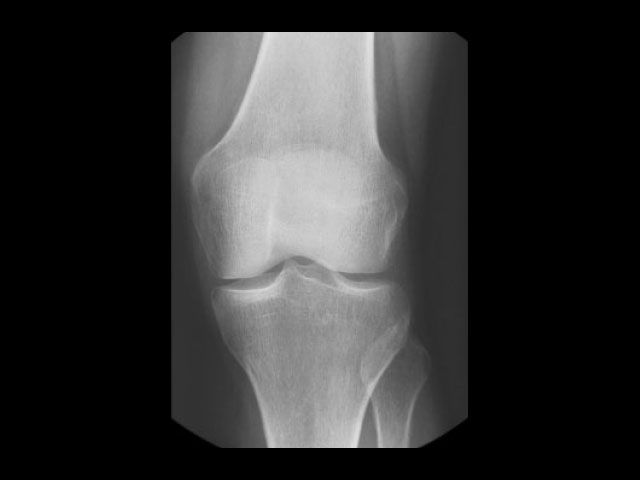

Ποτέ άλλοτε η απλή ακτινογραφία θώρακα και κοιλίας καθώς και η απεικόνιση των οστών δεν είχε την ποιότητα που επιτυγχάνεται με το σύστημα ICONOS.

Απεικόνιση 3